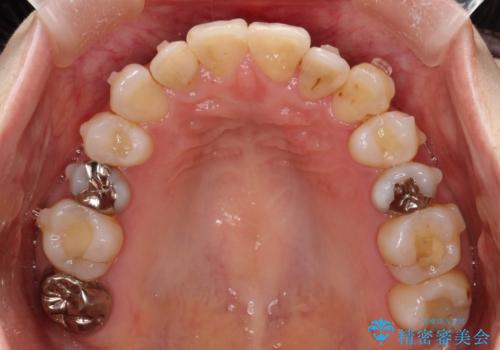

初診時の歯並びの状態としては、上下ともに前歯部中心としたの中等度のがたつき(叢生)があり、全特に左上の前歯は1本だけ引っ込んでおり、犬歯は外に飛び出した状態でした。

抜歯は行わず上顎の奥のスペースを利用して歯をスライドする方法の他に歯列弓の拡大やディスキング(歯と歯の間の隙間を作る処置)を行い叢生を改善しましています。

歯の大きさの不揃いが原因の正中のズレは、ディスキング量を調整することで合わせました。